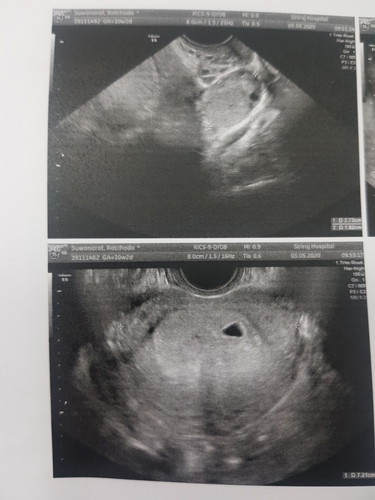

แท้งแล้ว

แฟนตั้งครรภ์ถ้านับตามอายุครรภ์ก็ 11 week แต่ยังเจอแค่ถุงตั้งครรภ์ ล่าสุดแฟนมีอาการเลือดซึมตั้งแต่เย็นวันที่7 วันที่8หาหมอ ได้ยามารับประทาน วันที่10 แฟนมีอาการปวดท้องรุนแรงรีบพาไปพบหมอ ปรากฏว่าร่างกายได้พยายามขับถุงตั้งครรภ์ออกมา หมอจึงจำเป็นต้องหยุดการตั้งครรภ์ T T